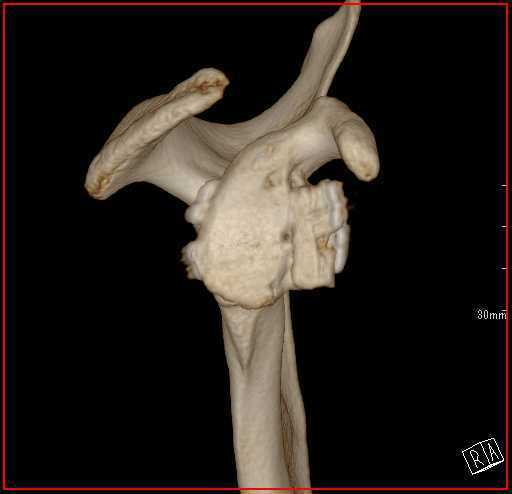

脱臼を繰り返すと、前方を支える軟部組織(関節唇、関節包)がさらに損傷していき、最終的には受け皿の骨(肩甲骨)が欠けて小さくなったり、上腕骨の後方に大きな骨欠損が生じたりします。その結果、スポーツ活動はもちろん、日常生活にも大きな影響が出て生活の質(QOL)が著しく低下してしまいます。

X線 ( レントゲン )や MRI (磁気共鳴画像)を用いて、骨の位置や周囲の軟部組織の損傷を確認します。必要に応じて CT 検査も行います。

関節窩骨欠損がある場合の手術法

AGR(鏡視下バンカート修復術+腸骨移植)

骨盤(腸骨)から骨を採取して、欠損した肩甲骨の関節窩にブロックを用いて移植します。その後、鏡視下バンカート修復術を行います。

骨欠損があり、早期復帰が重視される場合に選択します。